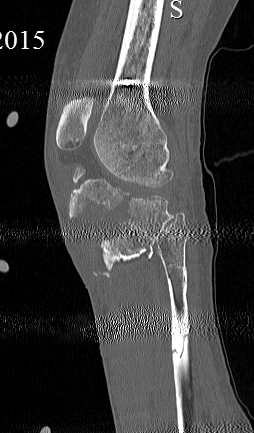

[Ortho] перелом проксимальной тибии + вывих бедра

Серия КТ сканов в аппарате